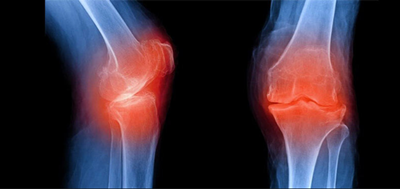

퇴행성관절염의 관절 경직은 일반적으로 아침과 휴식기 이후에 주로 나타납니다. 주로 나타나는 관절은 손가락 끝부분과 엄지손가락의 밑부분과 끝부분, 무릎, 엉덩이, 목, 등 아래쪽 등에서 진행이 많이 됩니다.

전문가들은 무엇이 퇴행성 관절염을 유발하는지 또는 왜 조직의 분해가 시작되는 아직 정확히 확인된바는 없다고 말하고 있습니다. 그러나 일단 이 상태가 진행되기 시작하면 관절의 다양한 부분을 손상시킬 수 있습니다. 연골, 힘줄과 인대, 뼈, 무릎 주변등의 손상이 진행될 수 있습니다.

관절 손상이 진행되면 관절 통증과 붓기, 운동 범위 감소 등이 발생하게 되고 통증이 시작되면, 시간이 지남에 따라 근육이 약해져 활동성이 현저히 떨어질 수 있습니다. 약한 근육은 관절을 지탱하지 못하고 결국 영향을 받은 관절은 변형이 될수 있습니다.

특히 퇴행성관절염은 주로 무릎, 엉덩이, 척추, 그리고 손에도 그 영향을 미칩니다. 기계도 오래 사용하면 닳듯이 사람 몸의 관절도 오래 사용하고 무리하게 사용하게 되면 보다 더 일찍 닳게 됩니다. 관절 손상은 되돌릴 수 없습니다. 하여 평소 건강한 체중을 유지하고 예방하는 활동을 통해 더 오래 삶의 질을 잘 유지하는 것이 지혜로운 삶이 될 것입니다.